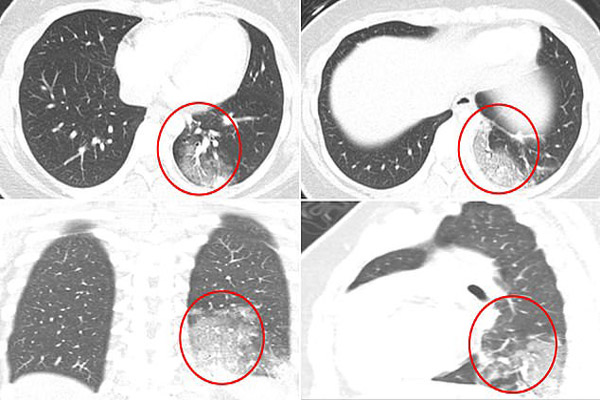

به گزارش جام جم آنلاین ، پزشکانی که CT اسکن کودکان کرونایی را بررسی کرده اند هشدار می دهند که این کودکان با آسیب های جدی ریوی مواجه می شوند.

این تیم از بیمارستان کودکان بوستون ، سی تی اسکن از موارد کودکان مبتلا به COVID-19 را برای دیدن نتایج و وضعیت ظاهری ریه ارزیابی کردند.

در یک مطالعه از 20 کودک تقریبا دو سوم آنها مبتلا به التهاب ریه ای شده بودند.

بخش دیگری از کودکان با مشکلات تنفسی شدید روبرو می شوند و کیسه های هوای موجود در ریه آنها مملو از مایعات می شود که بسیار خطرناک است.

در تصاویر سی تی اسکن ریه کودکان مشخص است که ریه آنها تحت تاثیر ویروس کرونا کدرتر شده است.